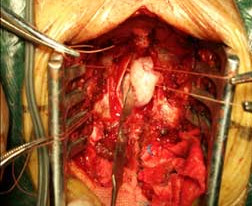

椎管內腫瘤 椎管內腫瘤術中